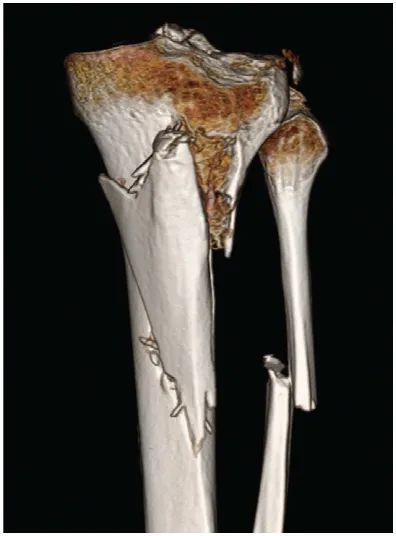

At presentation 1 week after injury, the patient was neurovascularly intact with resolving fracture blisters. The external fixator pin sites showed no evidence of infection. Radiographs showed a complex, largely extra-articular, proximal tibia fracture with dissociation of the tibial tubercle (Fig. 1). Subtle findings of a proximal lateral tibia avulsion fracture (a Segond fracture) and tibial spine comminution raised suspicion for ligamentous knee instability. Diastasis of the proximal fibula from the tibia demonstrated the high energy nature of the trauma. A computed tomography (CT) scan showed the complex proximal tibia fracture with a separate tibial tubercle fragment and confirmed a posterior cruciate ligament (PCL) avulsion fracture and lateral proximal tibia avulsion (Fig. 2). Magnetic resonance imaging (MRI) confirmed a lateral meniscal root tear, disruption of the PCL, proximal tibiofibular capsular ligaments, and moderate posterolateral corner injury (Fig. 3).

Figure 2: 3D CT reconstruction.